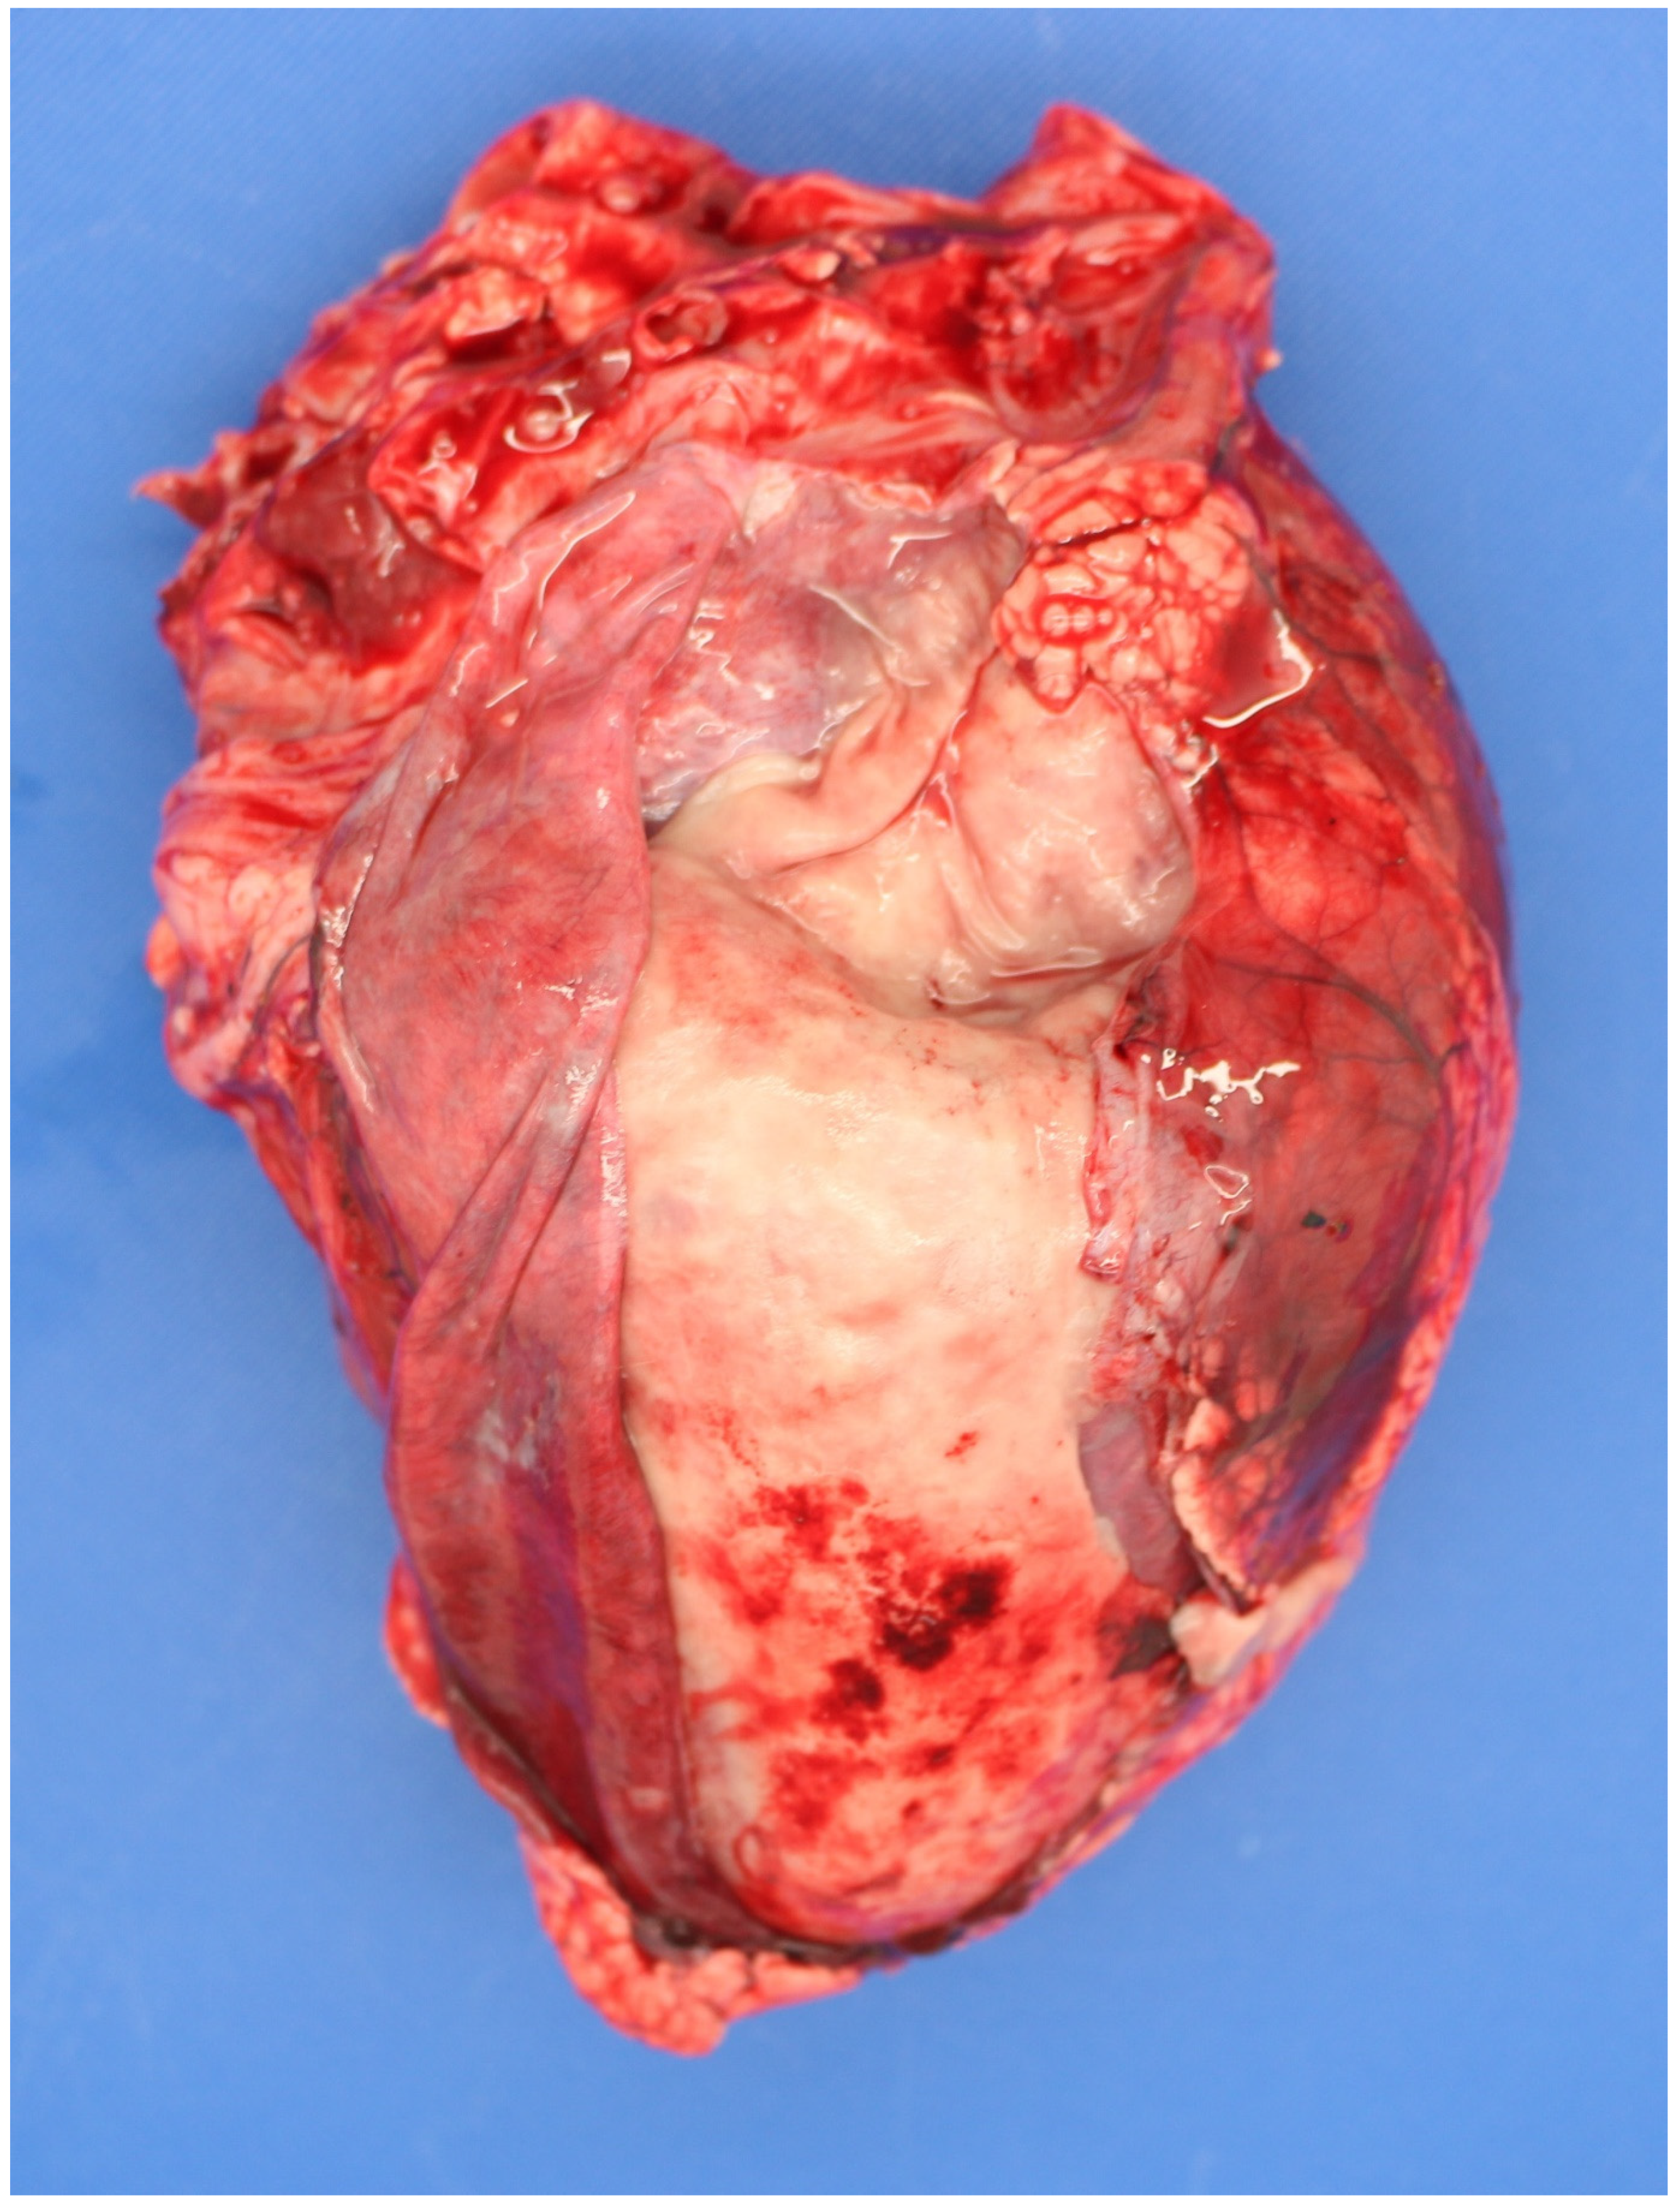

3.4.1. Sampling the Carcass

3.5. Examination of the Placenta